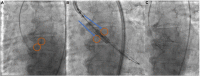

Since the first groundbreaking procedure in 2002, transcatheter aortic valve implantation (TAVI) has revolutionized the management of aortic stenosis (AS). Through striking developments in pertinent equipment and techniques, TAVI has now become the leading therapeutic strategy for aortic valve replacement in patients with severe symptomatic AS. The procedure streamlining from routine use of conscious sedation to a single arterial access approach, the newly adapted implantation techniques, and the introduction of novel technologies such as intravascular lithotripsy and the refinement of valve-bioprosthesis devices along with the accumulating experience have resulted in a dramatic reduction of complications and have improved associated outcomes that are now considered comparable or even superior to surgical aortic valve replacement (SAVR). These advances have opened the road to the use of TAVI in younger and lower-risk patients and up-to-date data from landmark studies have now established the outstanding efficacy and safety of TAVI in patients with low-surgical risk impelling the most recent ESC guidelines to propose TAVI, as the main therapeutic strategy for patients with AS aged 75 years or older. In this article, we aim to summarize the most recent advances and the current clinical aspects involving the use of TAVI, and we also attempt to highlight impending concerns that need to be further addressed.